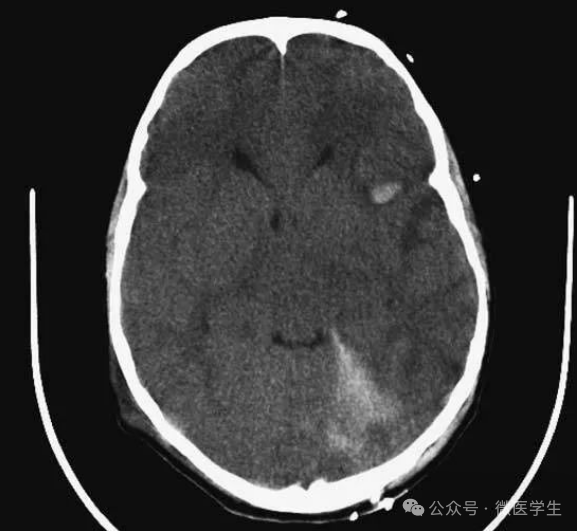

动脉瘤破裂导致蛛网膜下腔出血、

脑室积血、非交通性脑积水。

与外伤性蛛网膜下腔出血不同,动脉瘤破裂导致的SAH常不累及大脑凸面,而位于基底池附近。脑动脉瘤常位于鞍上池的Willis环血管。

A:四脑室积血;

B:中脑导水管、环池、右侧侧脑室颞角积血,前交通动脉处(动脉瘤好发位置)出血密度较高;

C:三脑室积血;

D-F:侧脑室积血,蛛网膜下腔出血(血液代替了脑脊液)。